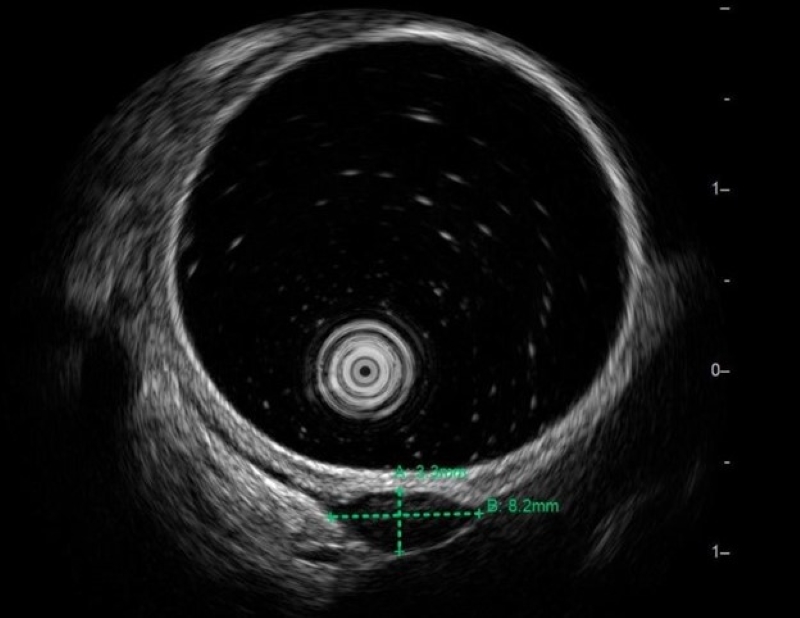

Trong quá trình nội soi dạ dày, bác sĩ phát hiện tại thân vị có một khối lồi kích thước khoảng 1cm, bề mặt niêm mạc bên trên bình thường, khi thăm bằng kìm sinh thiết thấy mật độ chắc, di động, nghĩ đến u dưới niêm mạc. Trước nghi ngờ tổn thương u dưới niêm mạc, các bác sĩ tiếp tục chỉ định siêu âm nội soi (EUS) - phương tiện chẩn đoán chuyên sâu giúp đánh giá chính xác bản chất khối u. Kết quả cho thấy khối u kích thước khoảng 8,2 x 2,2mm, xuất phát từ lớp cơ trơn, ranh giới rõ, cấu trúc giảm âm đồng nhất, không vôi hóa, không chảy máu. Các đặc điểm này gợi ý nhiều đến u cơ trơn lành tính, nhưng vẫn chưa loại trừ GIST, một tổn thương khác nguy cơ cao hơn.

Khối u được phát hiện trên hình ảnh siêu âm nội soi